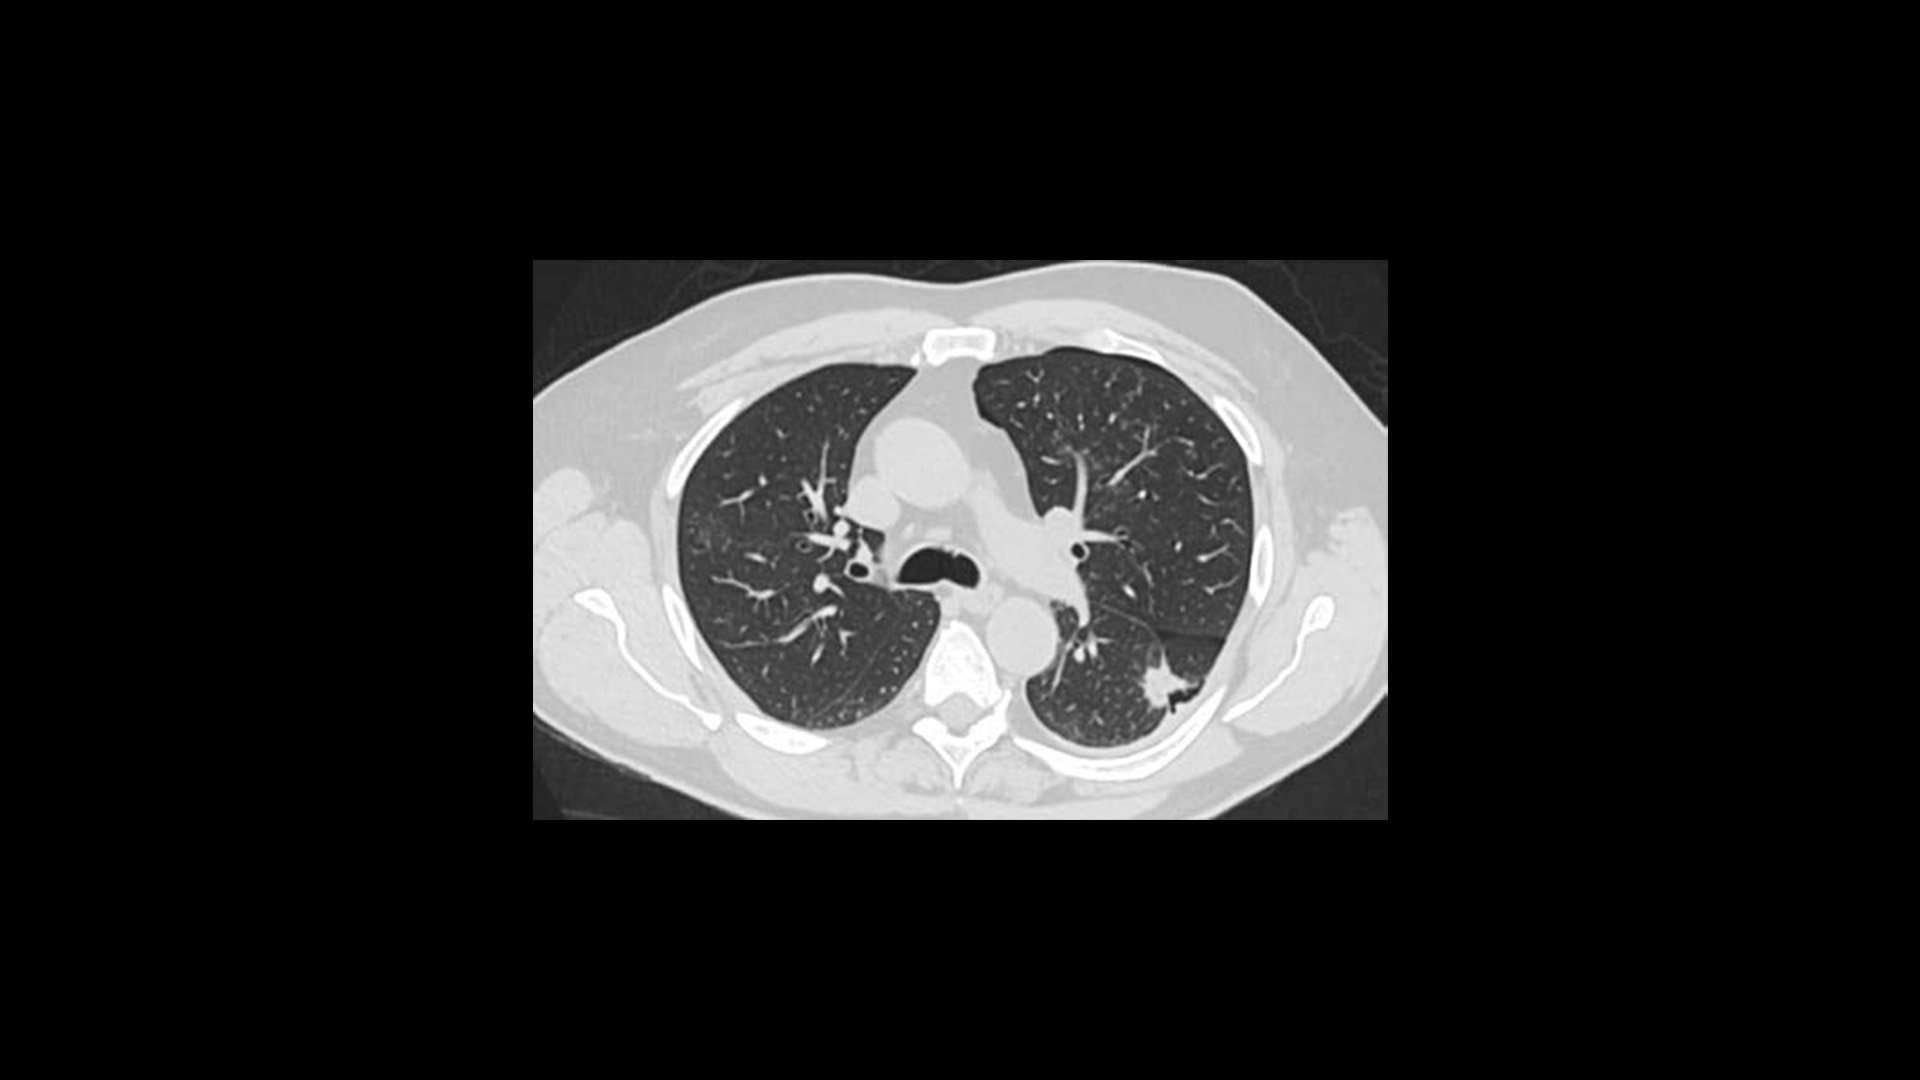

True Enhance DL

Designed to enhance what matters

True Enhance DL is a deep learning-based processing method intended for contrast enhancement of single energy images. True Enhance DL uses a dedicated Deep Neural Network (DNN) trained to estimate monochromatic, 50 keV GSI images from single-energy X-ray. This technology brings four deep learning models that the user can choose depending on different contrast enhancement phases by clinical tasks.